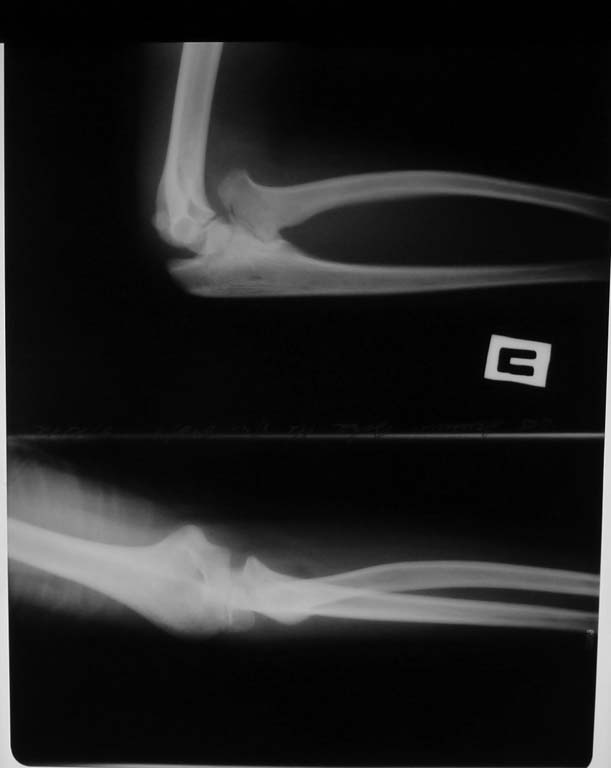

Больной 11 лет. В последние месяцы отмечается нарастание ограничения движений в локтевом суставе и предплечье. После получения незначительной травмы обратился в травмпункт.

Выявлен костно-хрящевой экзостоз, растущий в межкостный промежуток из проксимального конца локтевой кости, приведщший к вывиху головки лучевой кости, вторичной деформации шейки, формированию неоартроза между экзостозом и лучом.

Сгибание в локтевом суставе до 110 град, разгибание полное. Ротационные движения предплечья резко ограничены. Неврологии нет. Прилагаем снимки и КТГ.Мнения относительно оперативного вмешательства разделились.

Виноват, описался. Экзостоз, конечно же, лучевой кости. Прошу прощения.

Это не экзостоз. Это синостоз. Описан еще в 1793году Sandifort-ом. Ни один из приведенных вами способов успеха не даст - попробовать можно только резекцию синостоза с внедрением васкуляризированного лоскута между костями.

Данила, думаю все таки синостоз. Щель между костями еще прослеживается, но и она исчезнет. Чего только не внедряли между костями для реконструкции, даже целлофан. Лучше ничего не делать, конечно же.

Дальнейшее обсуждение не получится. Ребёнка соперировал шеф. Андрей Середа был прав. Это типичный радиоульнарный синостоз, что хорошо было видно в ране. Головка росла с отклонением кпереди, рентгенологически создавая картину вывиха. Вмешательство окончилось частичной остеотомией головки. удалена мешающая сгибанию её часть. На том всё и закончилось. Никаких реконструктивных вмешательств не предпринимали.